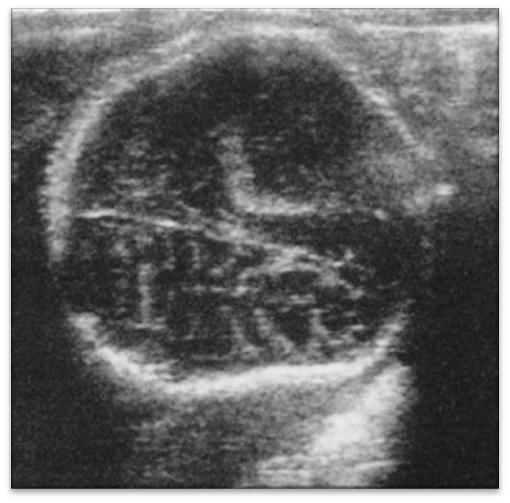

Osteogeneis imperfecta - skull demineralization